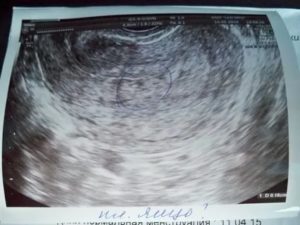

Так на УЗИ выглядит пустое плодное яйцо.

На ранних сроках крайне сложно выявить пустое плодное яйцо. Так как размеры эмбриона очень малы и его можно просто не заметить. Только по прошествии 5 недель, появляется возможность определить отсутствие плода.

Только на шестой неделе беременности пустое плодное яйцо можно диагностировать с помощью УЗИ. Оно проводится в любом случае, чтобы определить месторасположение плода, а также исключить внематочную беременность.

Анэмбриония на УЗИ